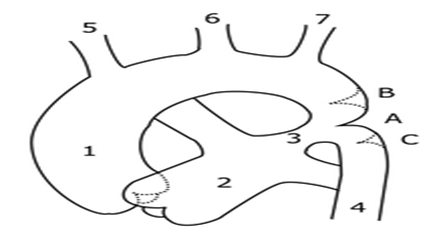

Coarctation of the aorta (CoA) is a congenital heart disease, it occur rarely during the life after trauma ,in cases of advance form of atherosclerosis of aorta and in Takayasu aortitis. CoA is defined as a constricted segment of thoracic aorta at the insertion of ductus arteriosus or a long segment of the hypoplasia of aorta..Sometimes coarctation may be in low segments of thoracic aorta and rarely on the abdominal aorta. It may occur with other form of valvular disease like bicuspid aortic valve, different levels of aortic stenosis or mitral valvular stenosis. In the past CoA has been described as preductal, ductal and postductal type (more common in adults) depending on whether the coarctation segment is proximal or distal to the ductus arteriosus, but now all are juxtaductal (the hemodynamic changes between 3 types are not significant) [1,2] (Figure 1).

Figure 1: Types of coarctation of aorta A-preductal B-ductal C-postductal.